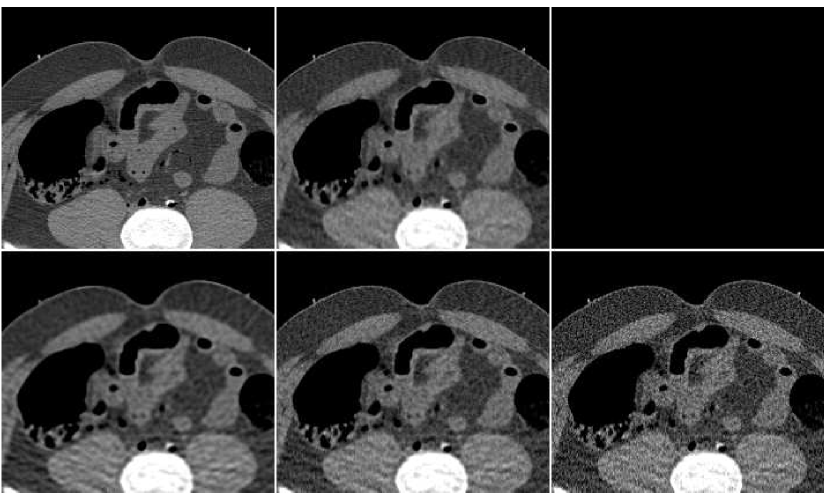

To summarize the fusion effect on the outcome of standard reconstruction algorithms, we display in Figure 12 images produced by both FBP and PWLS methods, before and after applying the proposed method of the ANN-based fusion; these images were previously given in Figures 6,10.

As a last experiment, we consider the special case where the ANN only performs a local filtering of the single version of the image, without a reference to the other versions. A neighborhood of radius ( pixels) was extracted for each location in the PWLS image, corresponding to iteration number . The fusion result is visually compared in Figure 14 versus the image produced from PWLS versions, as before. It can be observed that the processing by ANN reduces the noise appearing in the PWLS image, but it is slightly inferior to the fusion image produced from several PWLS versions.